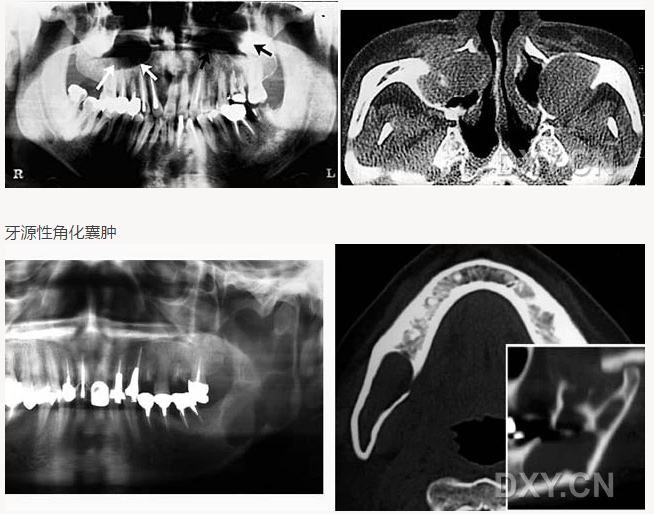

牙源性角化囊腫